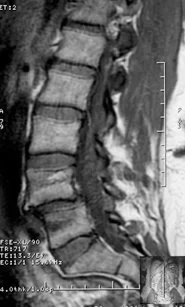

Spondylolisthesis is the forward slippage of one vertebra over the bone below it, most commonly occurring at the L4–L5 or L5–S1 levels of the lower back. The condition is primarily categorized as isthmic, involving stress fractures in the pars interarticularis (prevalent in young athletes), or degenerative, which results from age-related instability in older adults. To determine severity, specialists utilize the Meyerding Classification system, grading the slip from Grade I (less than 25%) to Grade V (complete displacement).